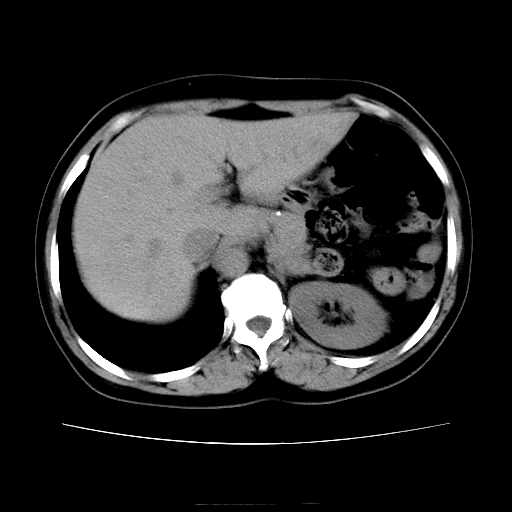

女45y多次(7次)碎石,结果不理想!曾碎石后尿出小碎石,仍腰痛,要求ct,其它不详.本人更倾向于钙化斑!无肾实质破坏,积水等提示集合系统无梗阻.另外腹腔多处钙化.是否结核后改变!谢谢赐教!

1)双肾结石。2)脾脏钙化灶。3)腹膜后多发淋巴结钙化。

尿路结石与腹部淋巴结钙化共存,建议v尿路造影检查,免得钙化灶冤枉为结石受罚。

考虑双肾结石,肾脏实质无破坏表现,没有结核病史,不考虑肾结核,